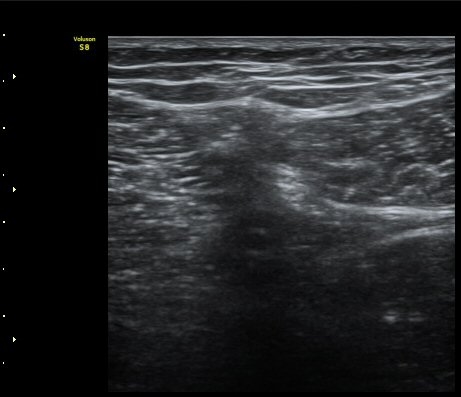

¹«¸­ ³»Ãø Á¾´Ü¸é°Ë»ç»ó ½ÉÇÑ °ñ±Ø°ú ¹Ý¿ù»ó¿¬°ñ Ç¥ÃþÀ¸·Î µ¹ÃâÀÌ °üÂûµÊ(»çÁø 1)

´ëÅð ³»Ãø, ¹«¸­ °üÀý¸é¿¡¼­ ¾à 10 cm ±ÙÀ§ºÎȾ´Ü¸é°Ë»ç¿¡¼­ ³»Ãø±¤±Ù°ú ºÀRHD±Ù(sartorius)

»çÀÌ¿¡¼­ º¹Àç½Å°æÀÌ °í¿¡ÄÚ Å¸¿øÇü ¾ç»óÀ¸·Î °í³ªÂûµÈ´Ù(»çÁø 2).

ŽÃËÀÚ¸¦ ¸»´ÜÀ¸·Î À̵¿ÇÏ´Ï º¹Àç½Å°æÀÌ ½½°³°ñÇϰ¡Áö¿Í  ºÀ°ø°¡Áö(sartorial branch)·Î

°¥¶óÁö´Â °ÍÀÌ °üÂûµÇ°í(»çÁø 3, 4, 5) µ¿¿µ»ó È­¸éÀ¸·Î º¸¸é ´õ¿í ¶Ñ·ÈÇÏ´Ù(÷ºÎ ÆÄÀÏ 1)

º¹Àç½Å°æ ½½°³°ñÇϰ¡Áö°¡ È®ÀÎµÈ »óÅ¿¡¼­ ´ëÅð ¾Õ¿¡¼­ ÃÊÀ½ÆÄÀ¯µµÇÏ ½½°³°ñÇϰ¡Áö

Â÷´ÜÀ» ½ÃÇàÇÏ¿´´Ù(÷ºÎ ÆÄÀÏ 2).